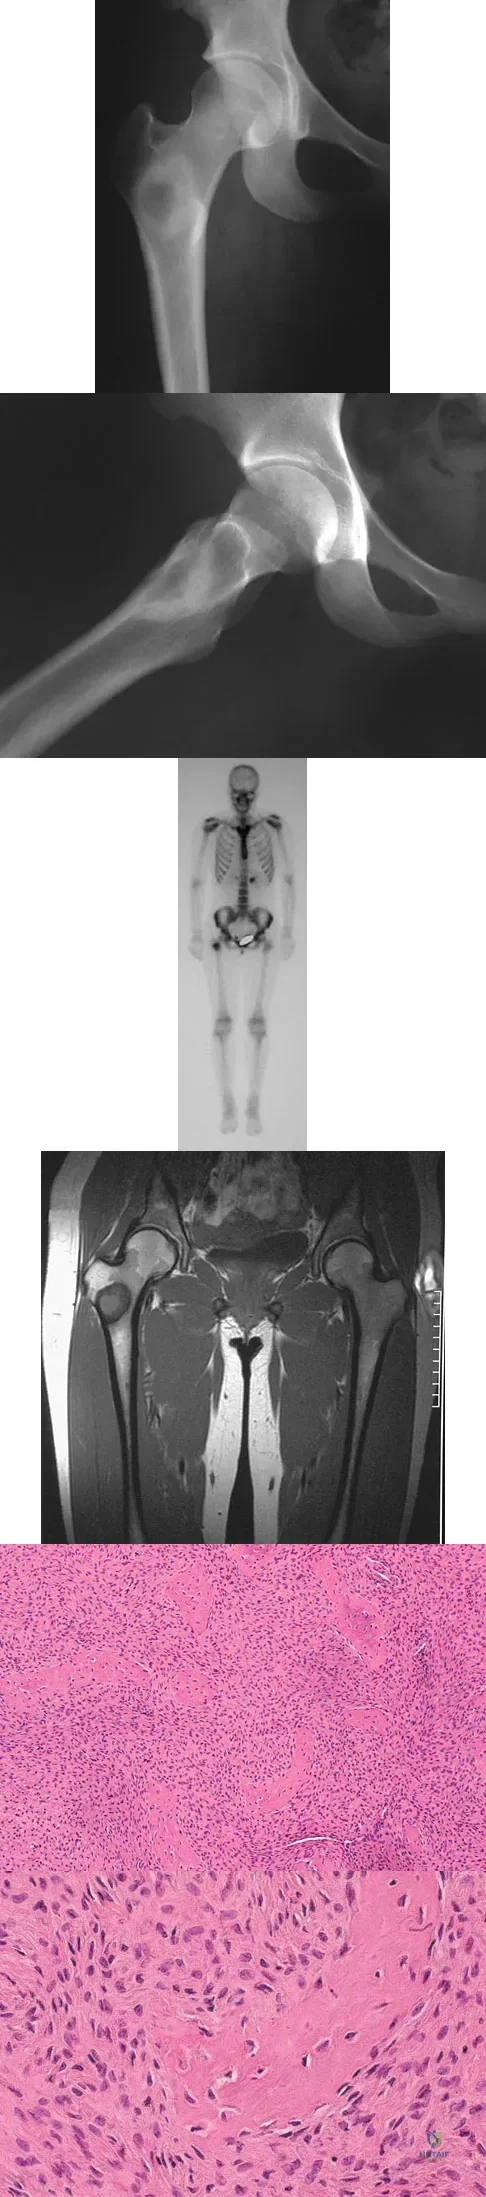

Question 61

A 16-year-old girl injured her hip in a fall. Radiographs are shown in Figures 14a and 14b. She denies any history of pain prior to the fall and is currently asymptomatic. A bone scan, MRI scan, and biopsy specimens are shown in Figures 14c through 14f. What is the most likely diagnosis?

Explanation